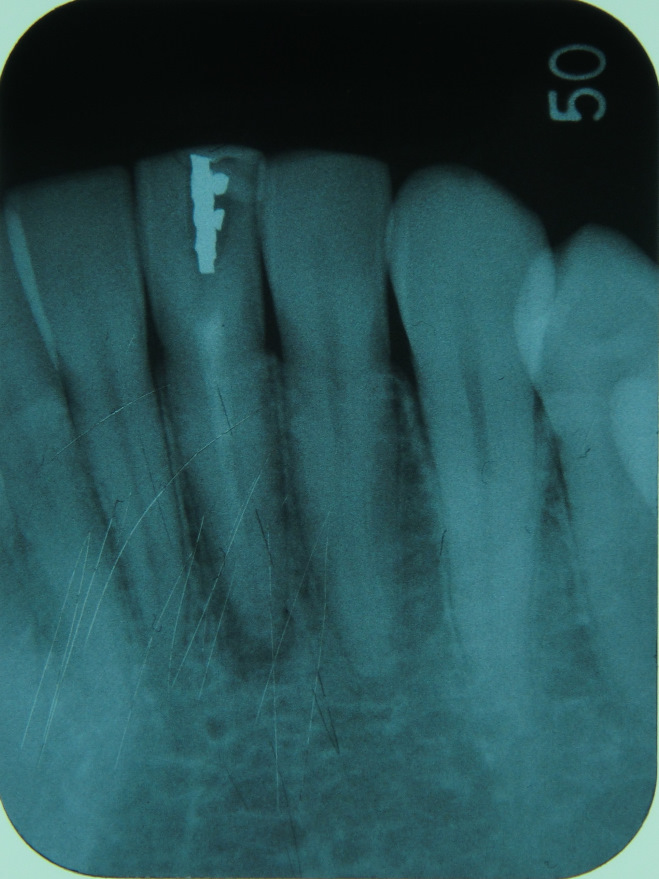

①レントゲンで確認し、被せ物が入っていたら除去する。このレントゲンでは、前回治療された根管充填が

不十分だということがわかります- ②前回、根管治療で詰めたゴム状の充填材や感染の原因となるものを除去する。当院では、超音波洗浄やco2レーザー・薬剤などを用いて根管内が無菌状態になるまできれいに処置します